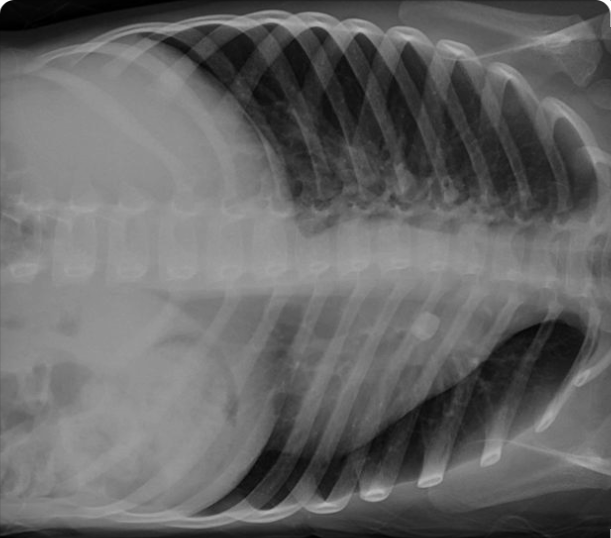

Medifyhome provides X-ray Chest Decubitus Left at affordable prices. An X-ray Chest Decubitus Left is a type of chest X-ray where the patient is positioned on their left side during the imaging procedure. This specific positioning helps in obtaining detailed views of the chest, especially when certain conditions need to be assessed more clearly than in a standard upright X-ray. The left decubitus position is typically used to evaluate the pleural cavity (the space between the lungs and the chest wall), especially for detecting conditions such as pleural effusion (fluid buildup in the pleural space), pneumonia, or lung collapse (atelectasis).

An X-ray Chest Decubitus Left is a type of chest X-ray where the patient lies on their left side to obtain a detailed image of the chest. This positioning is useful for assessing certain conditions, particularly those involving fluid accumulation or lung collapse.

An X-ray Chest Decubitus Left is performed to evaluate the chest for conditions that involve the accumulation of fluid or air, which shift with gravity when the patient lies on their side. This view is particularly useful for detecting pleural effusions (fluid in the pleural space) and pneumothorax (air in the pleural space), as these abnormalities become more apparent in the decubitus position. It is often used for patients who cannot stand or sit upright, such as those who are critically ill, bedridden, or recovering from trauma. By lying on the left side, fluid collects along the dependent (lower) side of the chest, while air rises to the uppermost part, making it easier to identify these conditions. This imaging technique is a valuable diagnostic tool for assessing chest abnormalities in patients who cannot undergo standard upright X-rays, providing critical information for diagnosis and treatment planning.